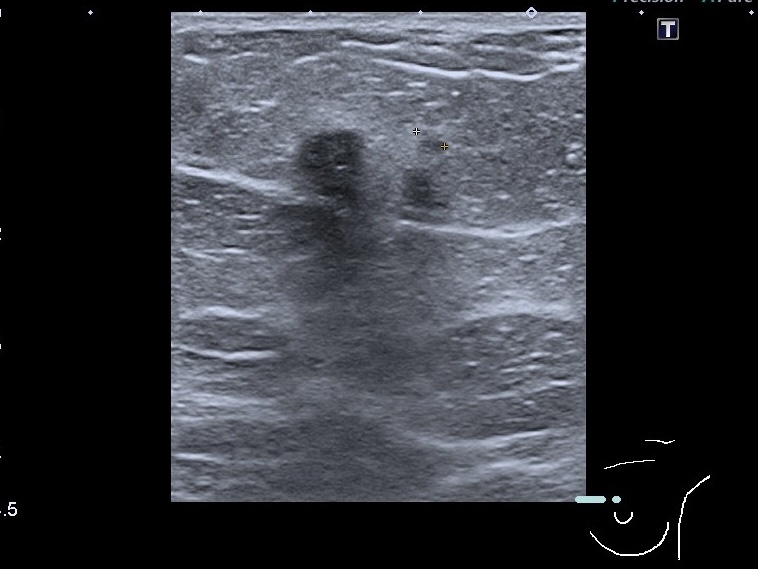

УЗД молочних залоз Medicinе groupПід час дослідження молочних залоз основну увагу лікар приділяє виявленню підозрілих утворень. УЗД молочних залоз особливо...

УЗД молочних залоз Київ. Крім різних видів пухлин молочної залози, нам часто зустрічаються також і запальні захворювання залози. Запальні неспецифічні...